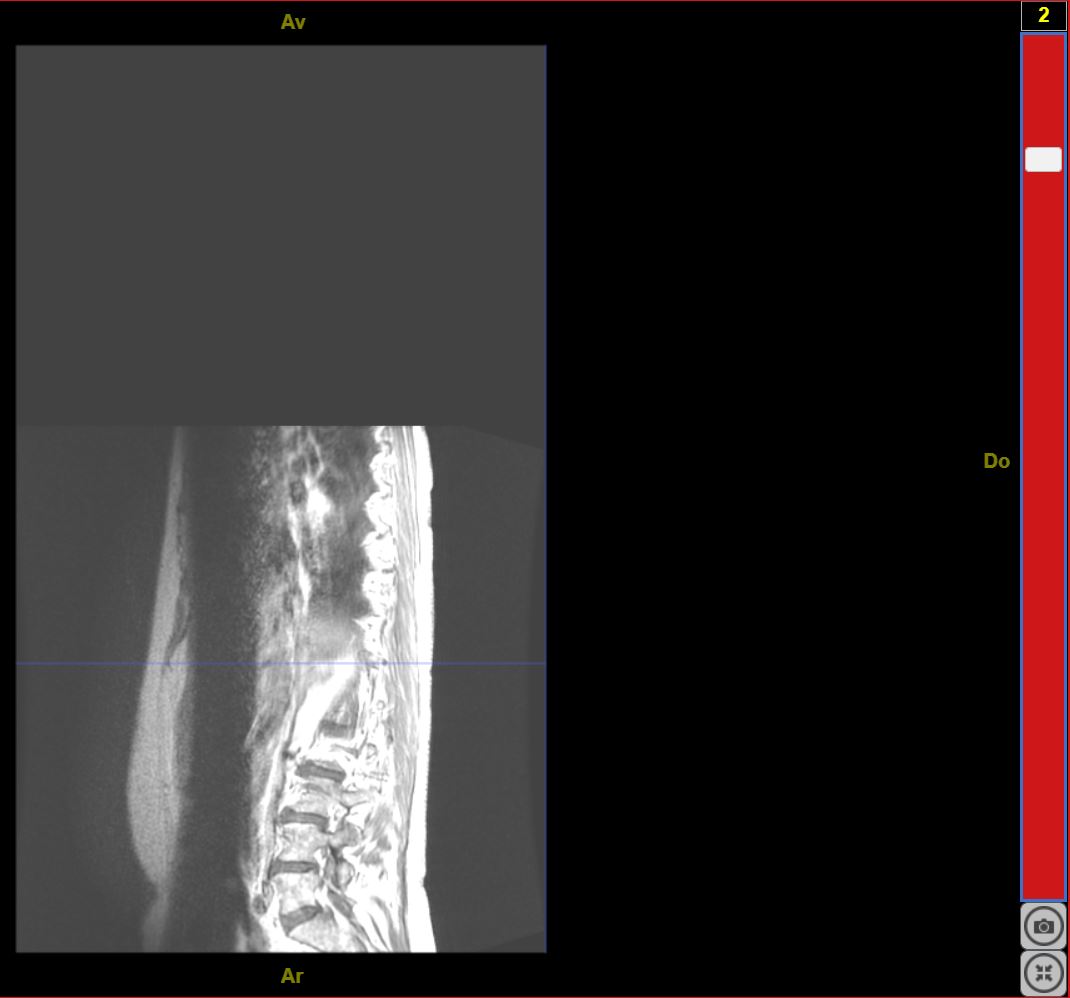

IRMsujet12132MoelleEpiniereSaineComplete T1Gado